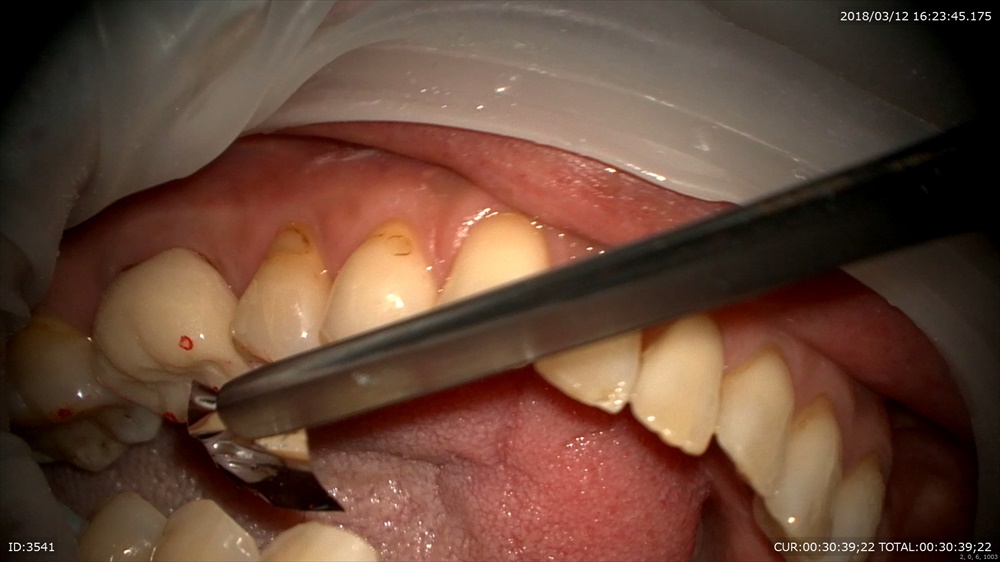

仮歯を

調整

これで噛めるか試験です。

当院が治療中、仮歯を必ず入れる理由は実際使って頂いて(本物と同じ形)大丈夫か判断するからです。

次回は精密な型をとります。